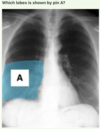

What anatomical feature is shown by pin A?

= D) Respiratory bronchiole